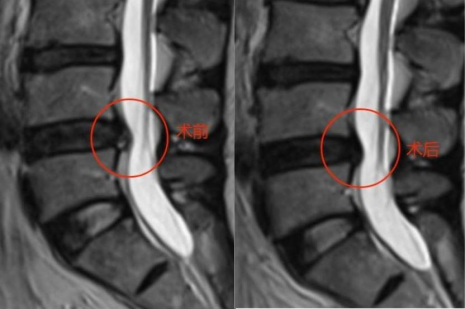

术前腰椎MR 可见腰4/5椎间盘中央偏左后突出,左后侧纤维环严重变薄,仅剩最外层纤维环完整。左侧侧隐窝狭窄,相应节段神经根受压。

术后3个月复查腰椎MRI,对比相同节段相同层面的图像,可见纤维环回缩明显,局部侧隐窝狭窄减轻,椎管狭窄减轻。

术后3个月复查腰椎MRI,矢状位显示原压迫神经根的椎间盘突出物显著缩小